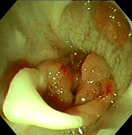

‣当院での症例紹介

炎症性ポリープ

炎症性ポリープ⑵